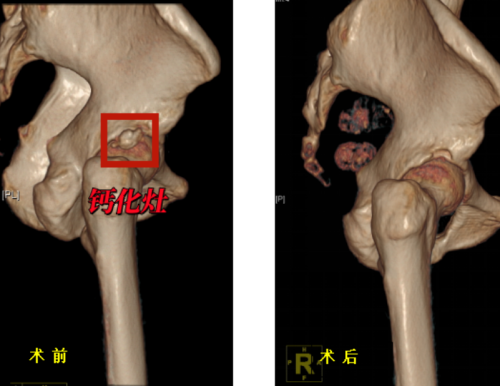

术前、术后三维CT对比示意钙化灶已清除

运动医学科门诊就诊,完善X线及核磁共振检查,考虑诊断为“右髋关节钙化性肌腱炎”并入院接受治疗。丑克主任团队为老人进行了髋关节镜微创手术,术后老人疼痛症状明显消退。老人开心地表示:“做完手术就不痛啦,效果立竿见影”。

治疗方面,保守疗法包括药物止痛、物理治疗、局部注射等方法。但由于钙化灶的存在,保守治疗往往只能暂时缓解症状,难以彻底解决问题,手术治疗则是更为直接有效的选择。通过关节镜微创技术清除钙化灶,修复受损肌腱。该手术具有创伤小、恢复快、直视下精准操作、清除彻底,效果立竿见影、并发症少,安全性高等优点。